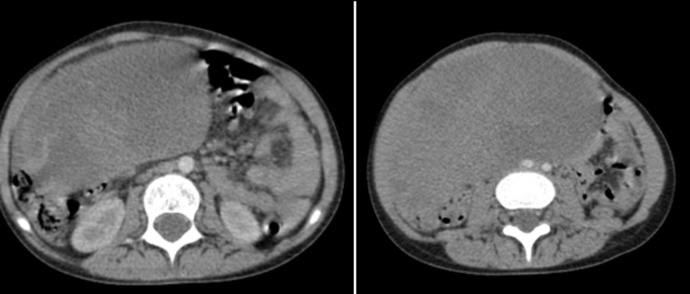

This case presents an 8-year-old girl diagnosed with B-cell acute lymphoblastic leukemia (B-ALL), who relapsed after 3 years of treatment and 1 year of complete remission, with an unusual extramedullary relapse in the ovary. Ovarian relapse of B-ALL is extremely rare in children, making this case noteworthy in scientific literature. The patient had an initial diagnosis of B-ALL with a deletion of chromosome 12, a genetic alteration previously associated with the ETV6-RUNX1 fusion gene, which is typically linked to a favorable prognosis but also carries a 20% risk of late relapse. The relapse was initially asymptomatic and went undetected until clinical symptoms of pelvic pain appeared. Imaging with pelvic ultrasound confirmed the ovarian involvement. The relapse was treated with standard chemotherapy protocols for B-ALL, resulting in a partial response. This case underscores the importance of considering extramedullary relapse in the differential diagnosis for pediatric ALL patients who present with atypical symptoms after remission. It also suggests that routine pelvic ultrasound could be a useful tool for early detection of ovarian and other extramedullary relapses, which are often associated with bone marrow relapse. The main take-away from this case is the necessity for vigilant follow-up, including targeted imaging, in ALL patient's post-remission to ensure early identification of extramedullary relapses, which can otherwise be easily overlooked. The presence of chromosome 12 deletion and its association with late relapse highlights the need for ongoing surveillance even in patients with initial favorable genetic abnormalities.